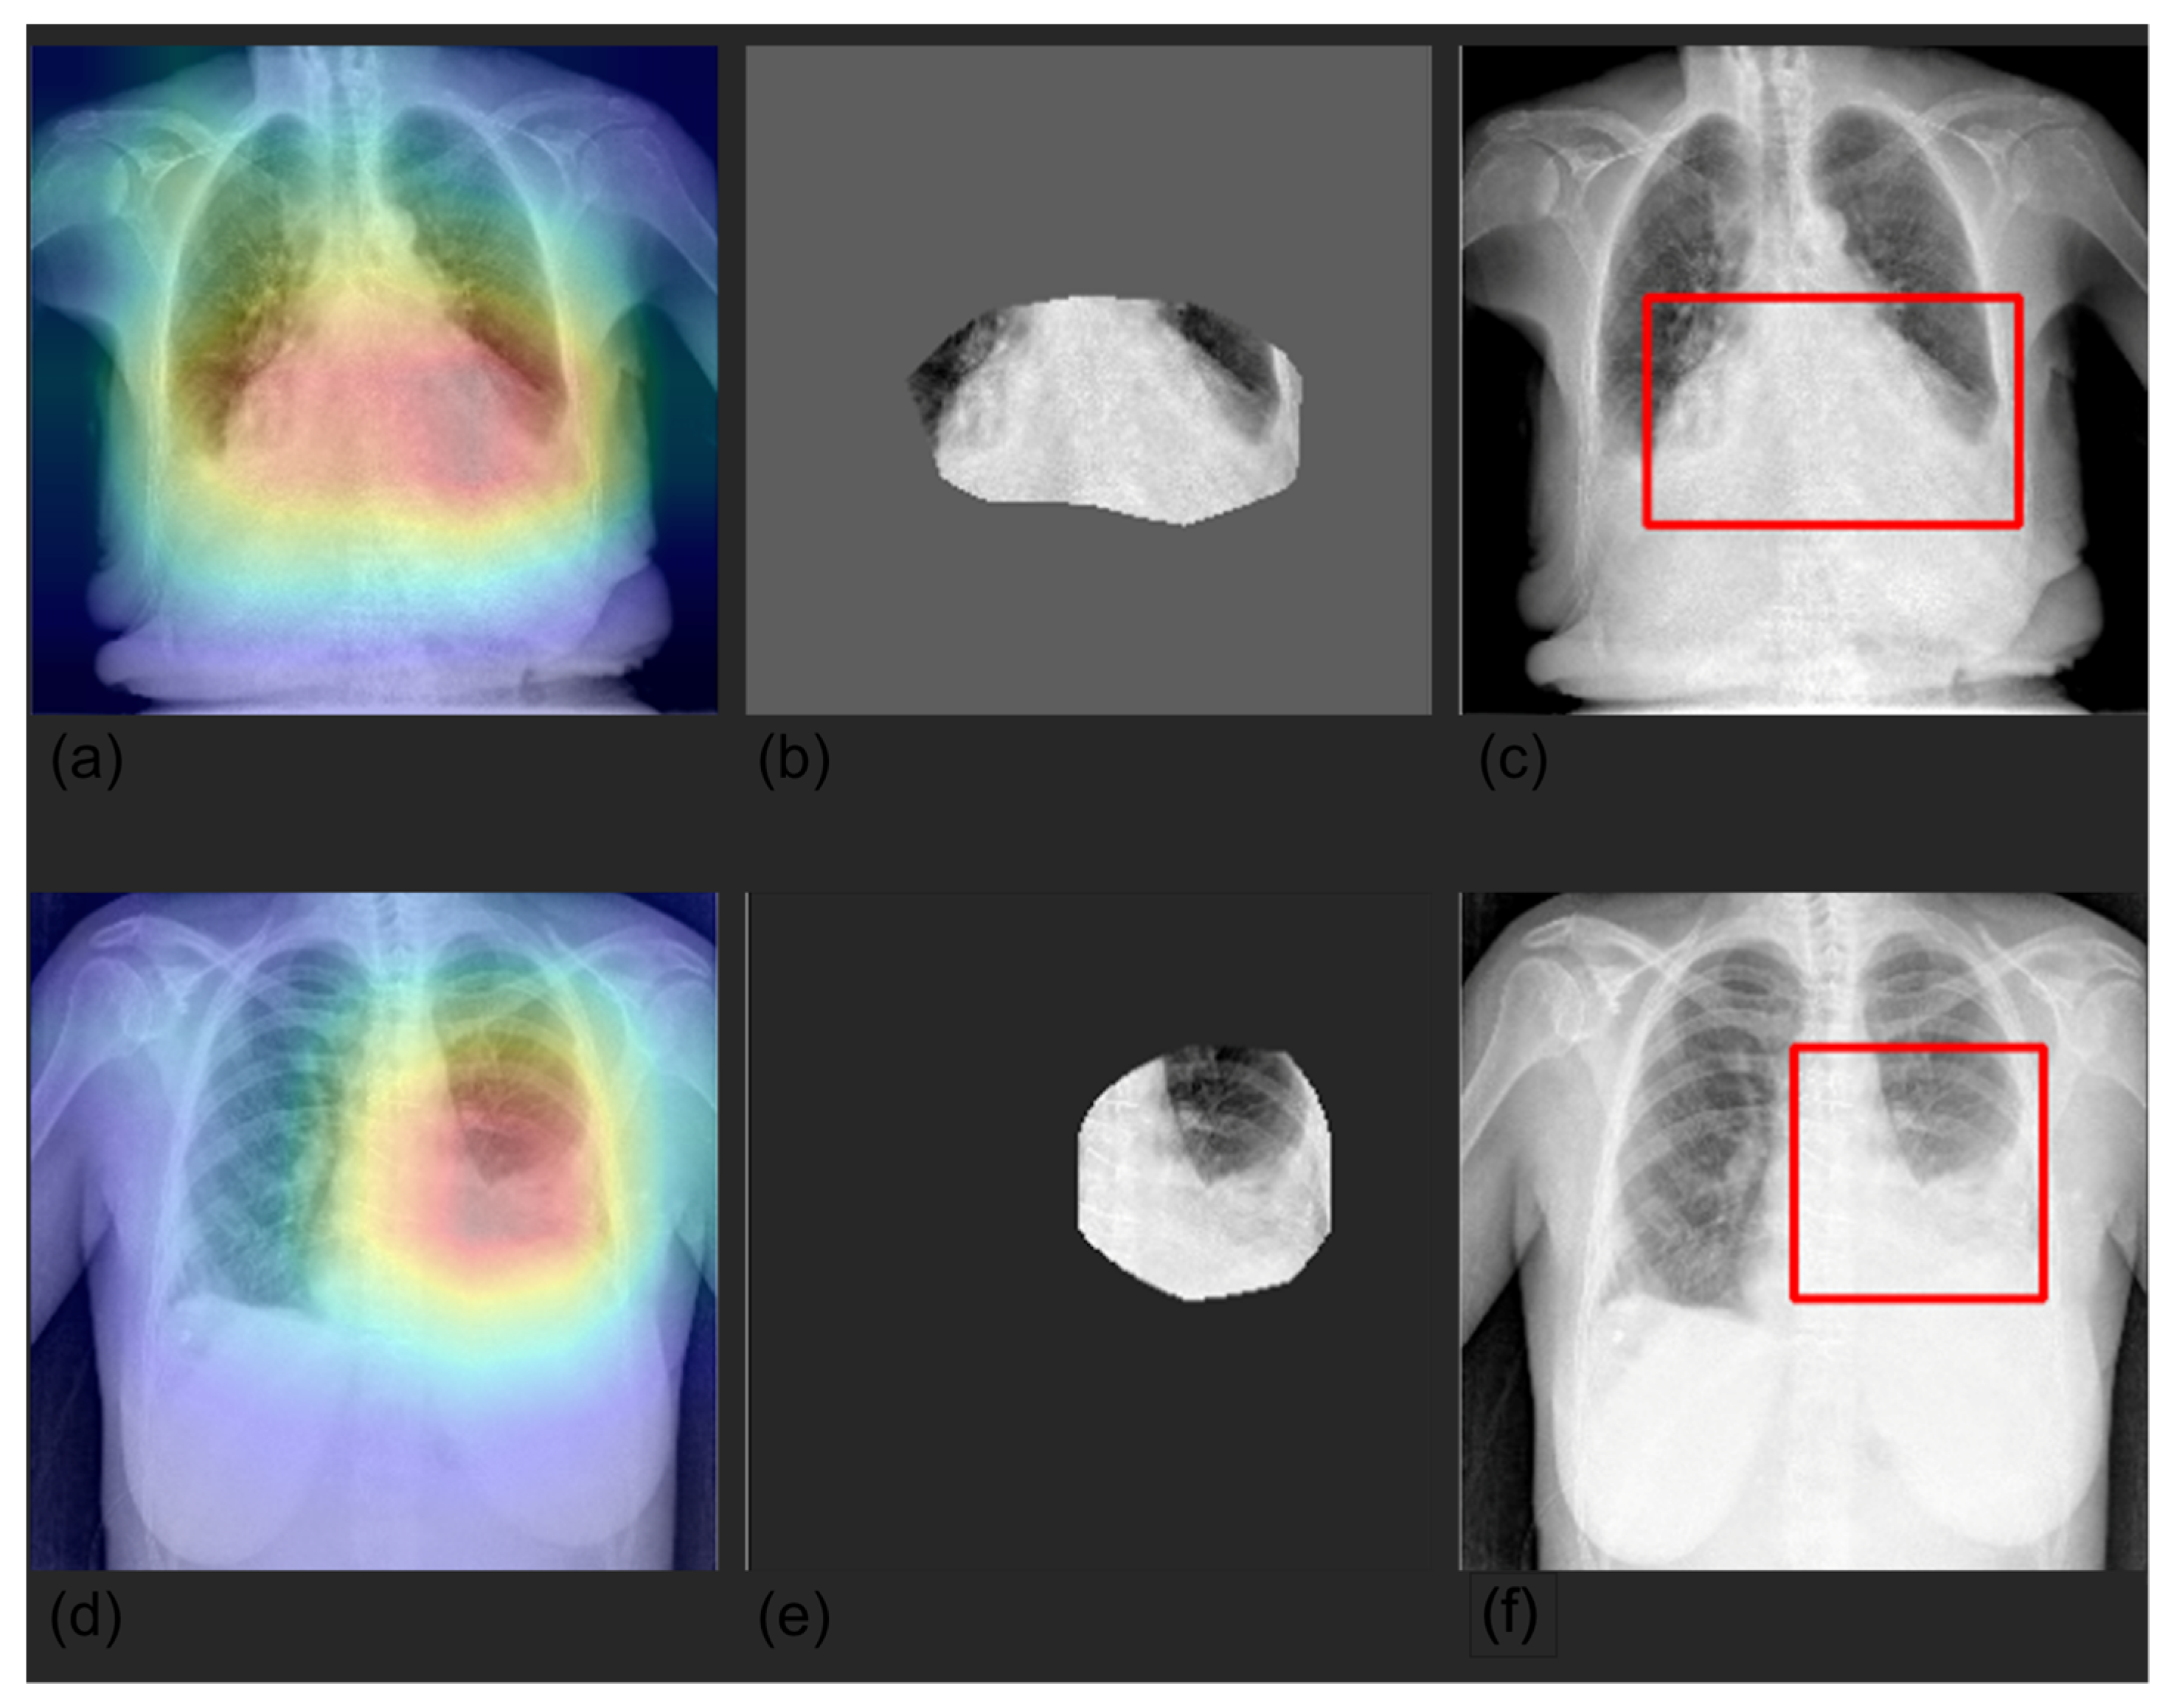

3.4. Grad-CAM